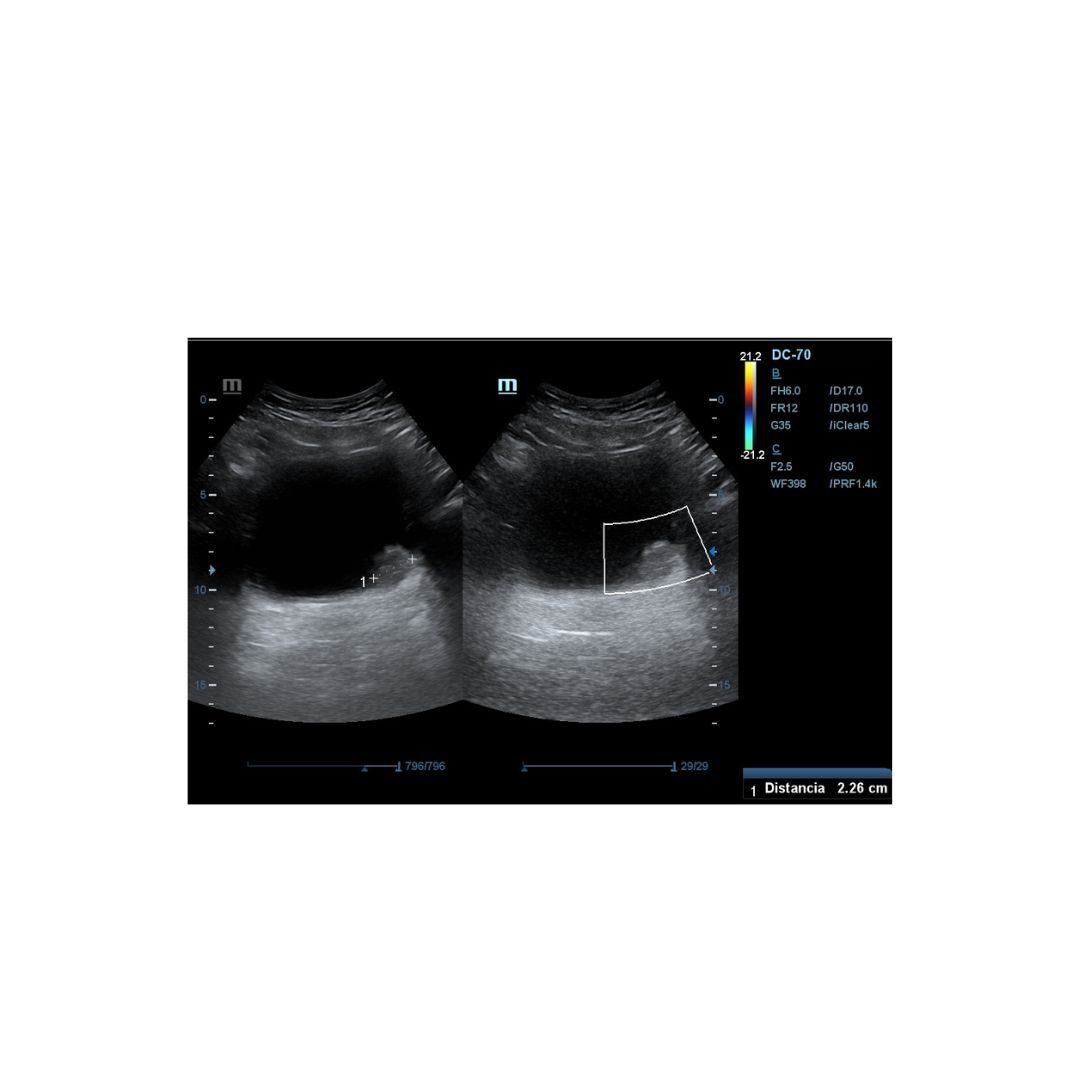

Es derivado a consulta de ecografía de nuestro centro de salud, donde realizamos Ecografía clinica abdominal, apreciándose imagen hiperecogénica pediculada en pared posterior izquierda de la vejiga vejiga, fija, que mide 2,26 mm aproximadamente en su eje mayor, sin captación Doppler.